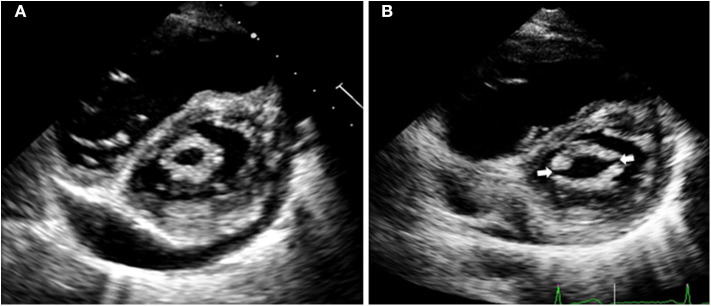

Figure 1.

Echocardiographic images of a patient with severe mitral stenosis before percutaneous mitral commissurotomy (A). After the procedure (B), both commissures are open (arrows), which increases the mitral valve area resulting in immediate hemodynamic improvement.